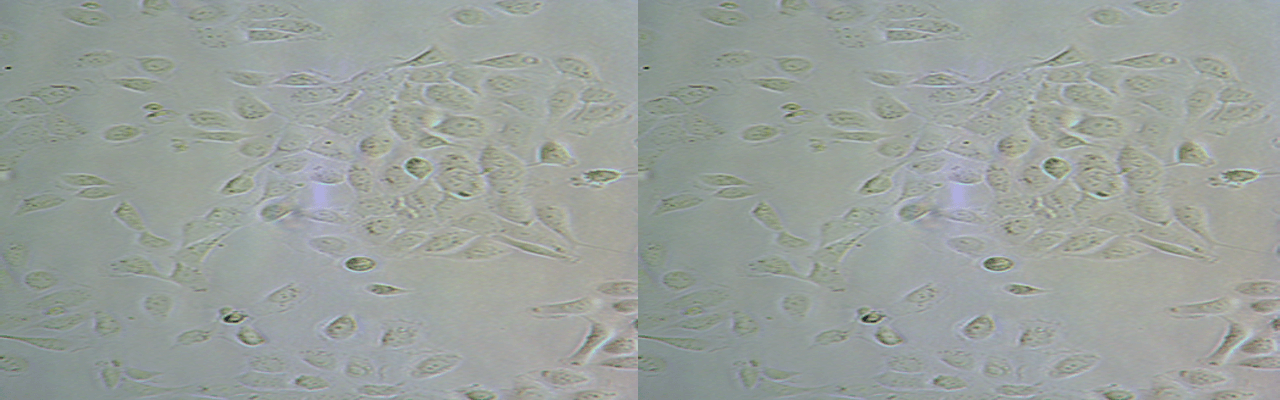

| 名称 | SK-LU-1 |

| 细胞全名 | 人低分化肺腺癌细胞 |

| 生长特性: | 贴壁生长 |